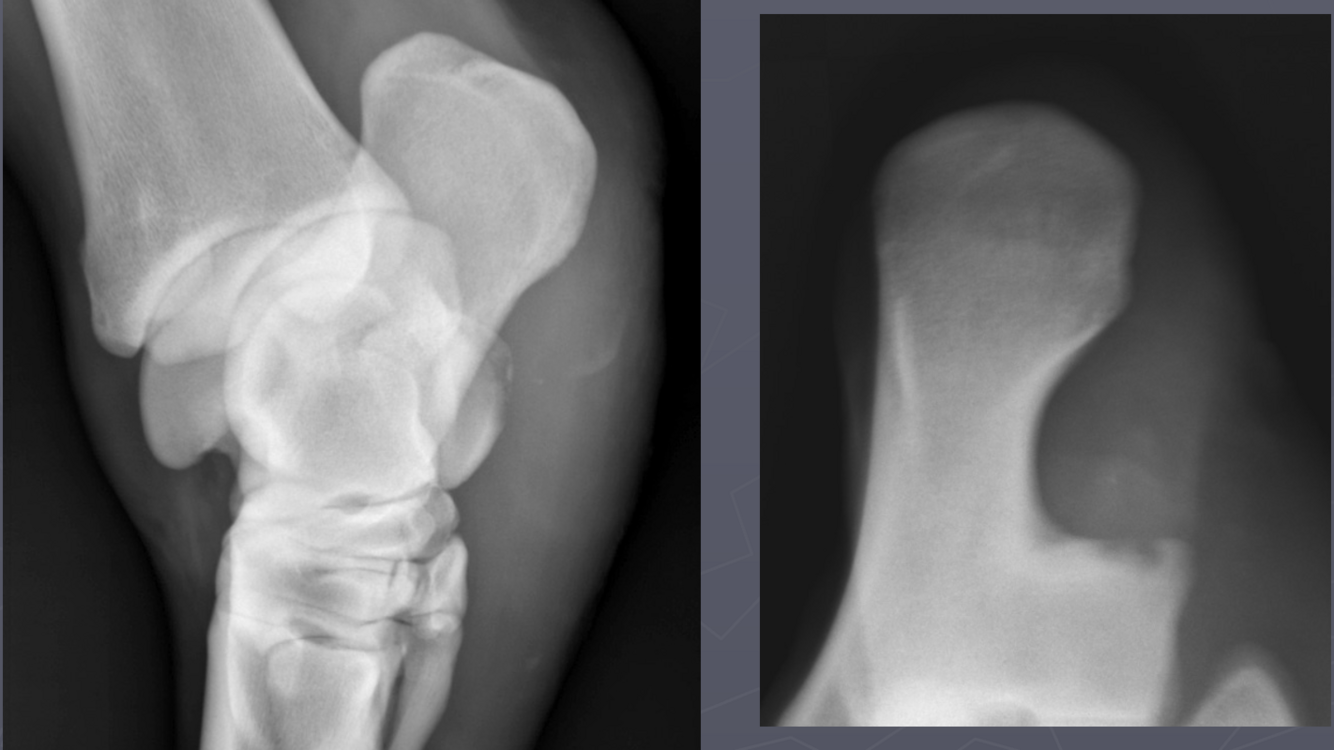

What is shown in these images?

Left: osseous cyst-like lesion, lysis, DJD, and fragmentation Right: osseous cyst-like lesion, flattening of condyle, DJD (less so than left image)